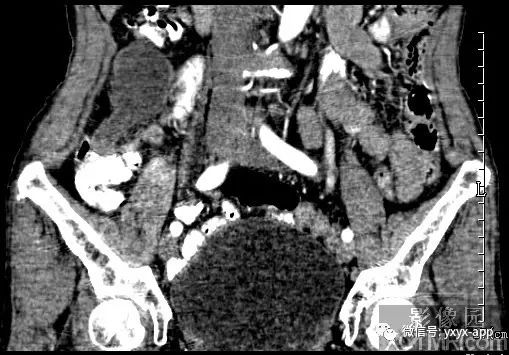

【病史临床】女性,66岁,右下腹胀痛不适一月。

CT影像表现:右下腹囊性肿块,囊液密度均匀,囊壁规整,增强囊壁有强化,周围肠腔无梗阻征象,考虑阑尾粘液囊肿或肠系膜囊肿。

最后结果:手术病理:阑尾粘液囊肿。

B超在阑尾粘液囊肿者可显示具有内回声的囊性肿物,囊壁变薄,且囊壁上有钙盐沉积,在腹膜假粘液瘤者可显示为粘液样腹水回声。CT在粘液囊肿可显示为右下腹包裹较好的壁薄囊性肿物。